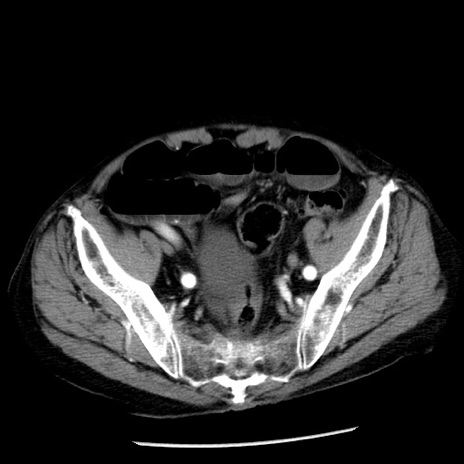

症例26(横断像)

【症例】80歳代男性

【主訴】嘔吐

【現病歴】昨晩2回嘔吐あり、今朝になっても嘔吐あり。来院。

【既往歴】胃潰瘍

【身体所見】意識清明、BT 37.6℃、BP 166/95mmHg、HR 100bpm、SpO2 97%、腹部:平坦・軟、腸蠕動音聴取良好、圧痛なし。

【データ】WBC 21900、CRP 1.46